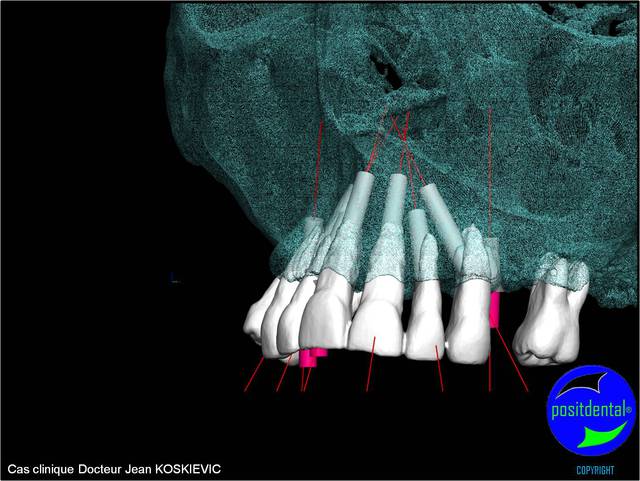

3D maxillaire inférieur et photo

Mci - Eugenol